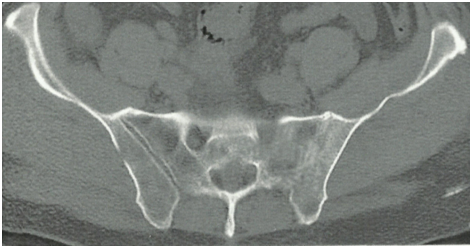

Radiological changes in the form of SIJ destruction/sclerosis (x-ray, CT) were evident in 10 of the 13 patients. MRI evidence of SIJ infection was noted on STIR sequence images in all 13 patients. The pathogens isolated were Staph. aureus in 69% (9 patients), streptococci in 23% (3 patients), and E.coli in 7% (1 patient).

Figure 2 left SIJ showing low signal intensity (edema and suppuration) and irregular joint outline (denoting destruction) on T1 MRI.